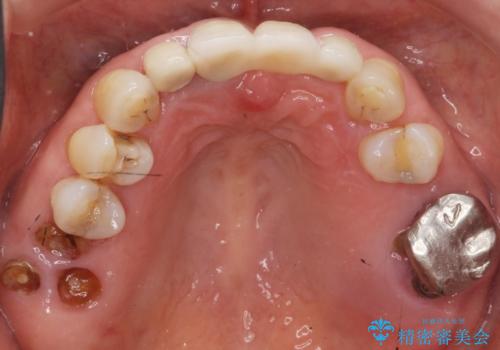

抜歯後歯肉の治癒を十分に待ったのち、ブリッジによる補綴治療を行いました。

歯周病が重度であったため抜歯後の歯肉の陥凹が大きく、GBRや歯肉移植による歯周組織の再建をおすすめしましたが、ご希望されませんでした。

- ¥1,010,000 (仮歯×9本、ファイバーコア×1本、ジルコニアクラウン スタンダード×9本)費用は治療当時の料金となります

自然な仕上がりと使い心地に喜んで頂けました。

奥歯の治療もやりたいとおっしゃって下さり、今後進めていく予定です。